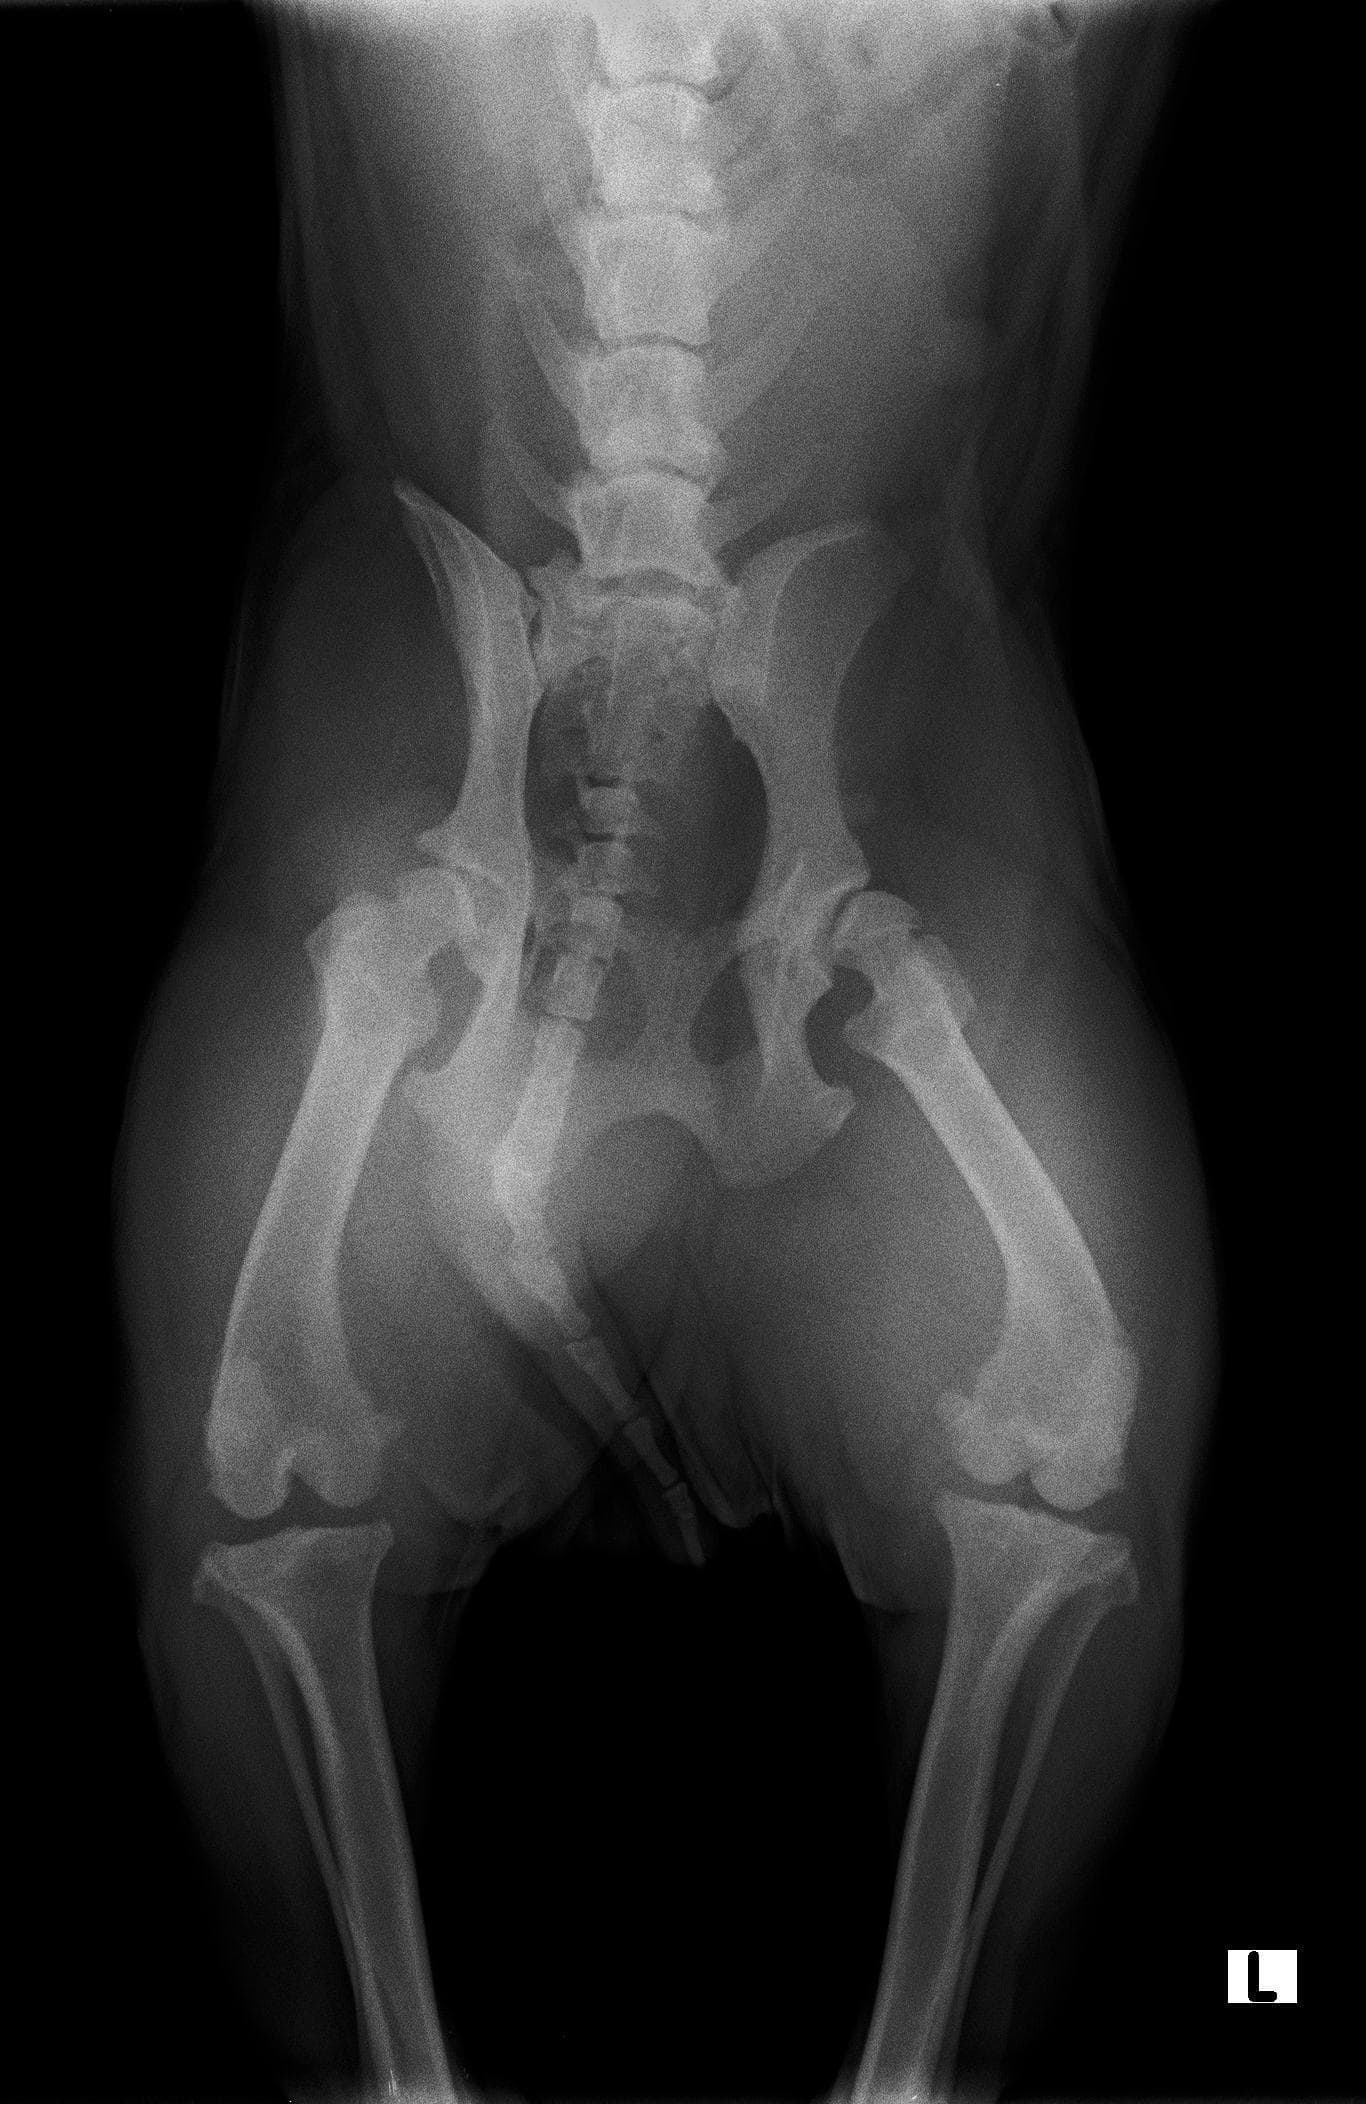

Hello, I am looking for a second though on my dogs bone conditions. She all of a sudden today couldn't walk. The pet accomodation messaged to tell.me this midday. I had her X rated and apparently she has both Hip Dysplasia and Spondylosis. 1. From the phoso of each can you indicate level of severity in each case and how long they potentially been present for? 2. Indicate which of the two is causing her not to walk Thank you

Hello and thank you for contacting Petco Pet Education Center, formerly Petcoach. There is severe hip dysplasia present in both hips, I am afraid. The left hip id also subluxated and I suspect it is causing more discomfort than the right hip. Hip dysplasia is a disease that dogs are born with. Arya must have had it sine a puppy but most likely it was not as severe as now. Spondylosis in the lumbar spine is usually a result of infection of intervertebral disc. Typically, it is an accidental finding in dogs that do not cause mobility problems. However, CT scan of the spine would give more detailed information about the severity of spondylosis.